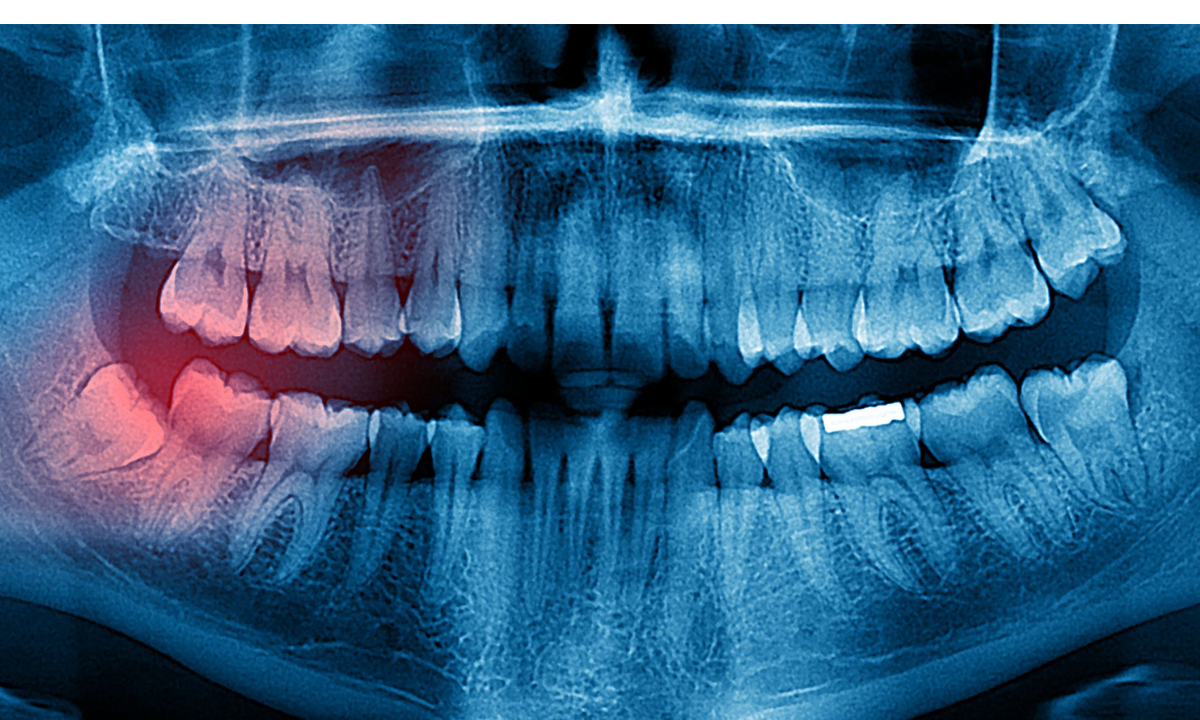

Wisdom Tooth Infection: 10 Warning Signs To Watch Out For

Wisdom tooth infection is one of the most common dental problems faced by young adults and adults alike. At our dental clinic in Whitefield, we